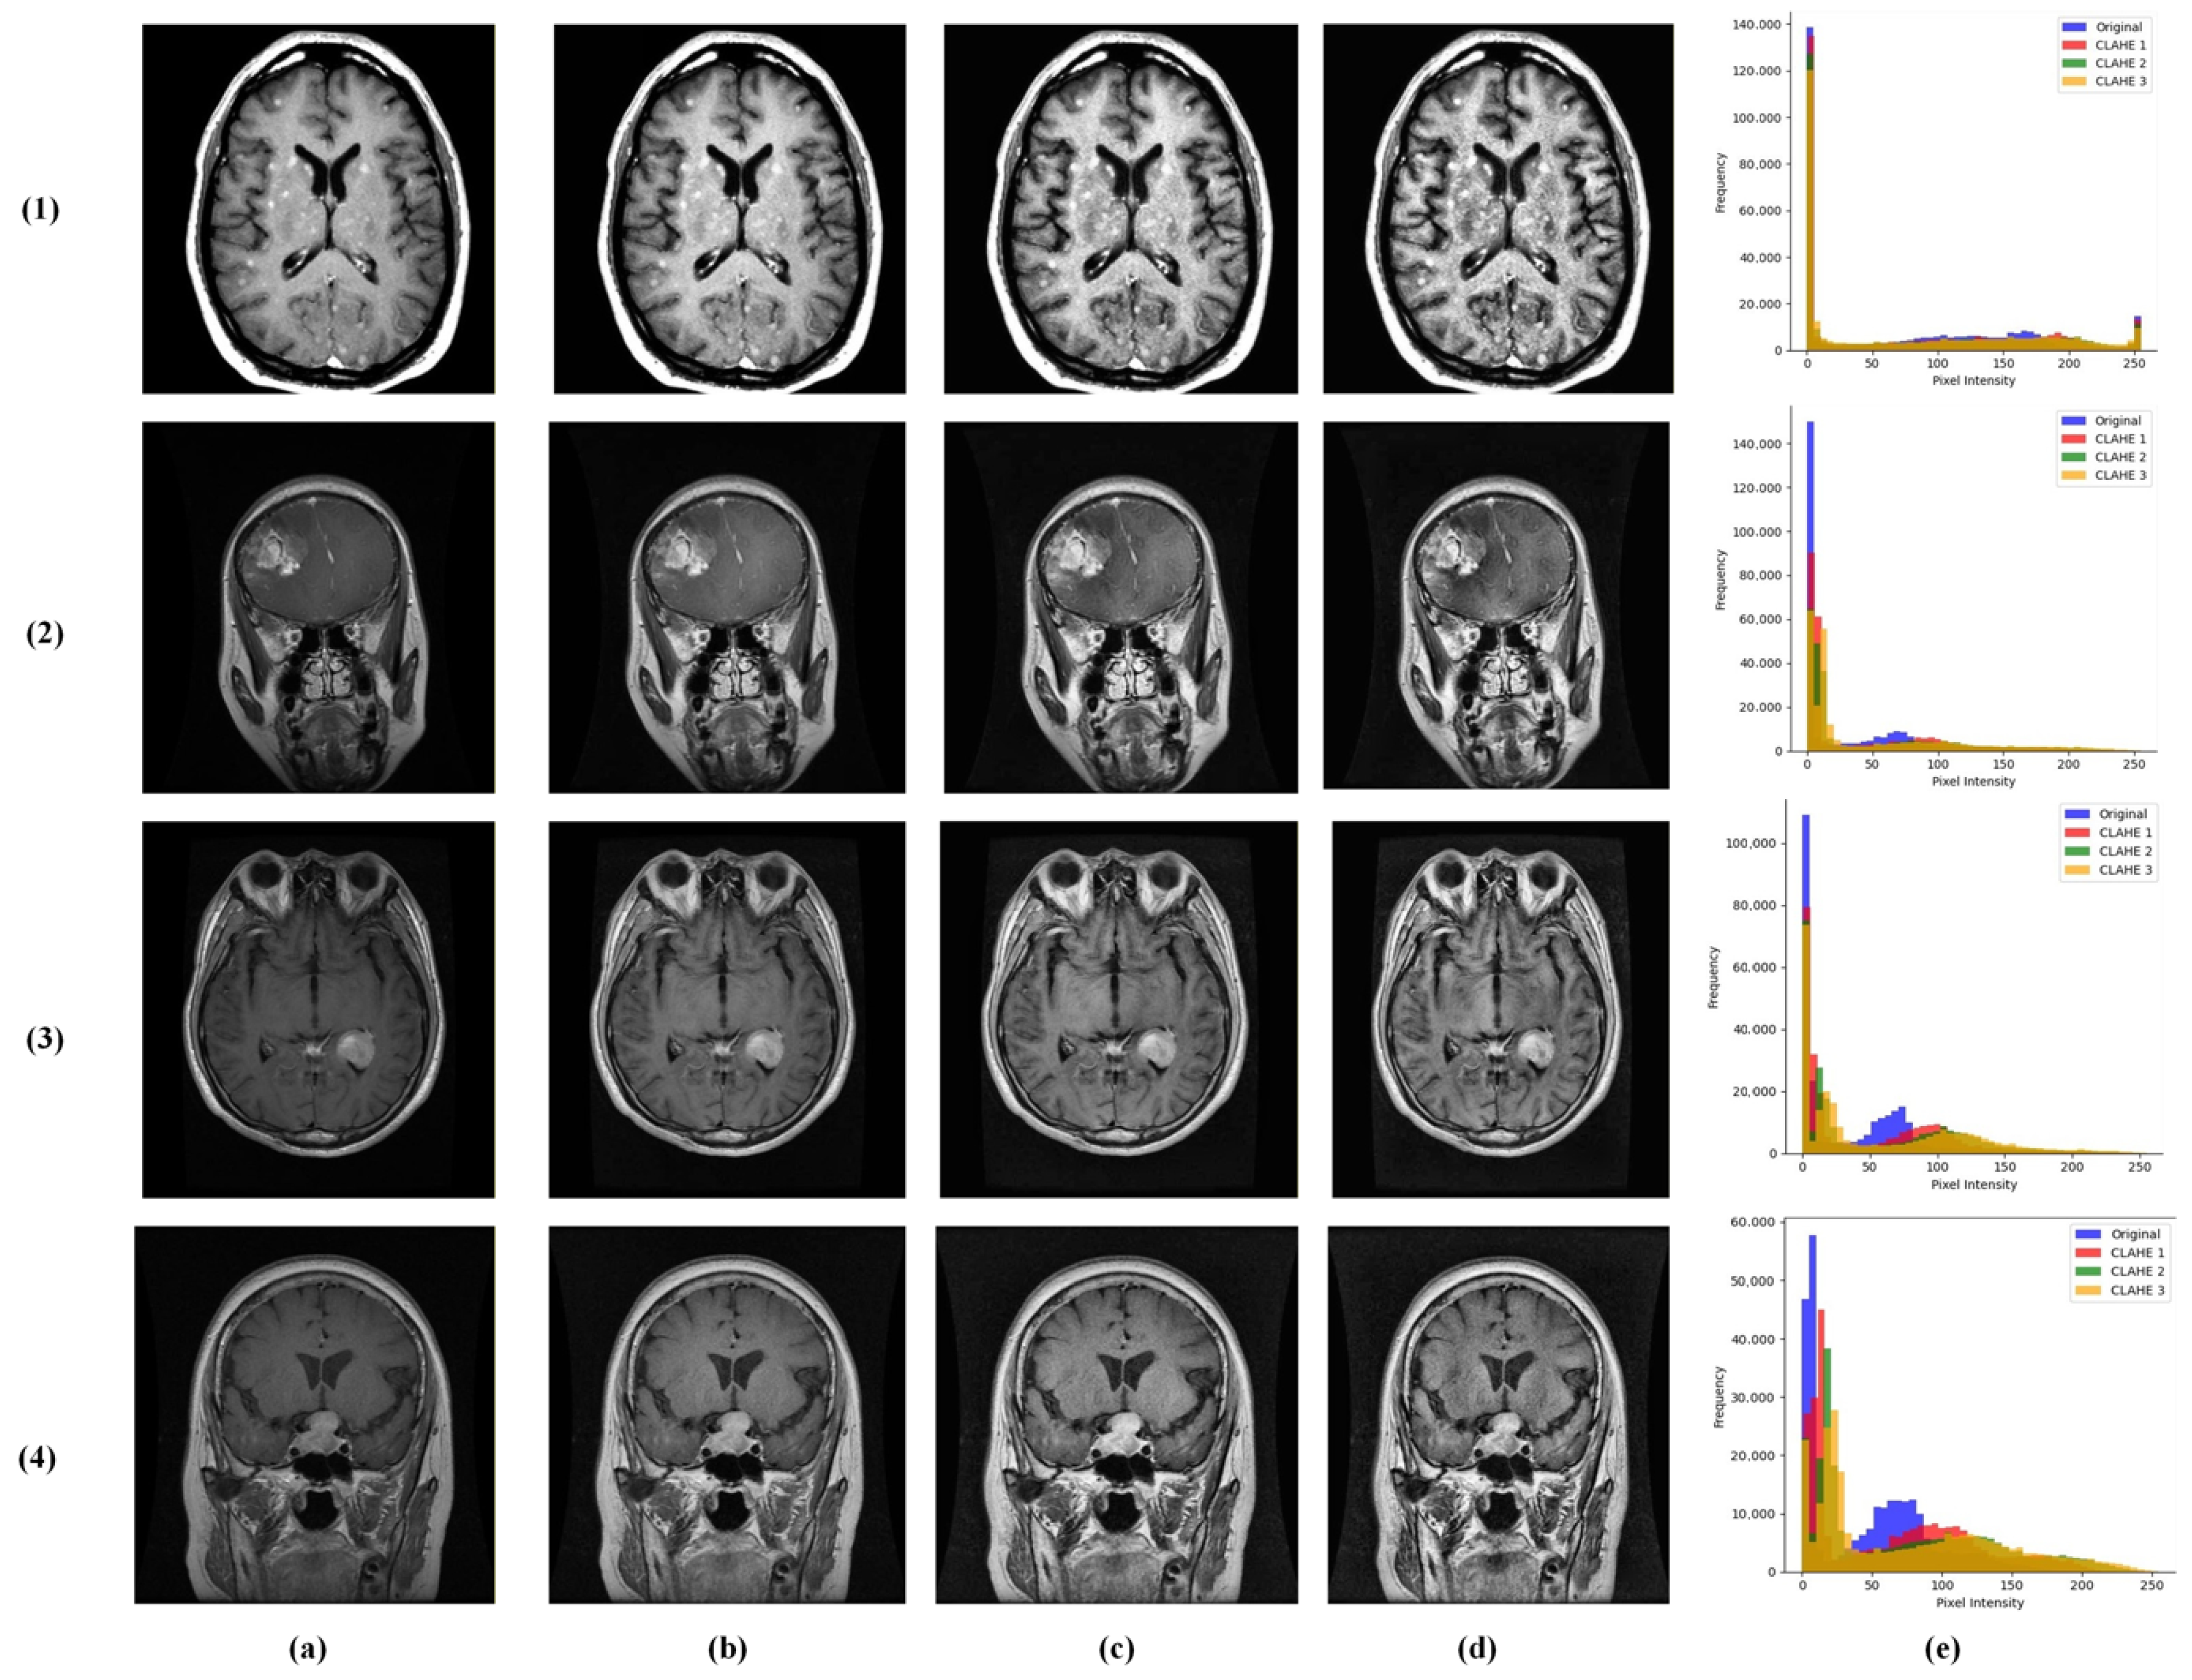

We introduced a multi-contrast CLAHE enhancement strategy implemented using the OpenCV library [23]. Each grayscale MRI was processed through the following three CLAHE configurations: conservative (clipLimit = 1.0, grid = 4 × 4), moderate (clipLimit = 2.0, grid = 8 × 8), and aggressive (clipLimit = 3.0, grid = 12 × 12). These were stacked as separate channels, providing the model with complementary contrast perspectives for robust feature learning (Figure 3).

Figure 3.

Visualization of multi-contrast CLAHE preprocessing results across the following brain tumor classes: (1) no tumor, (2) glioma, (3) meningioma, and (4) pituitary tumor. Columns represent (a) original input MRI, (b) conservative CLAHE, (c) moderate CLAHE, (d) aggressive CLAHE, and (e) histogram.